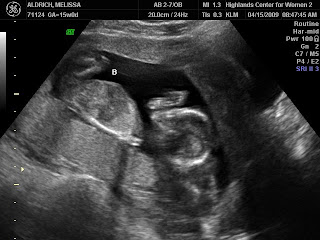

2009I had my second OB appointment last week and was just amazed to see how much the little ones had grown over the last month! They went from looking like little aliens:

to looking like sweet babies!

The miracles of God knitting little ones in my womb is just incredible to watch by ultrasound!

Do you think they’ll be identical or not based on these photos?